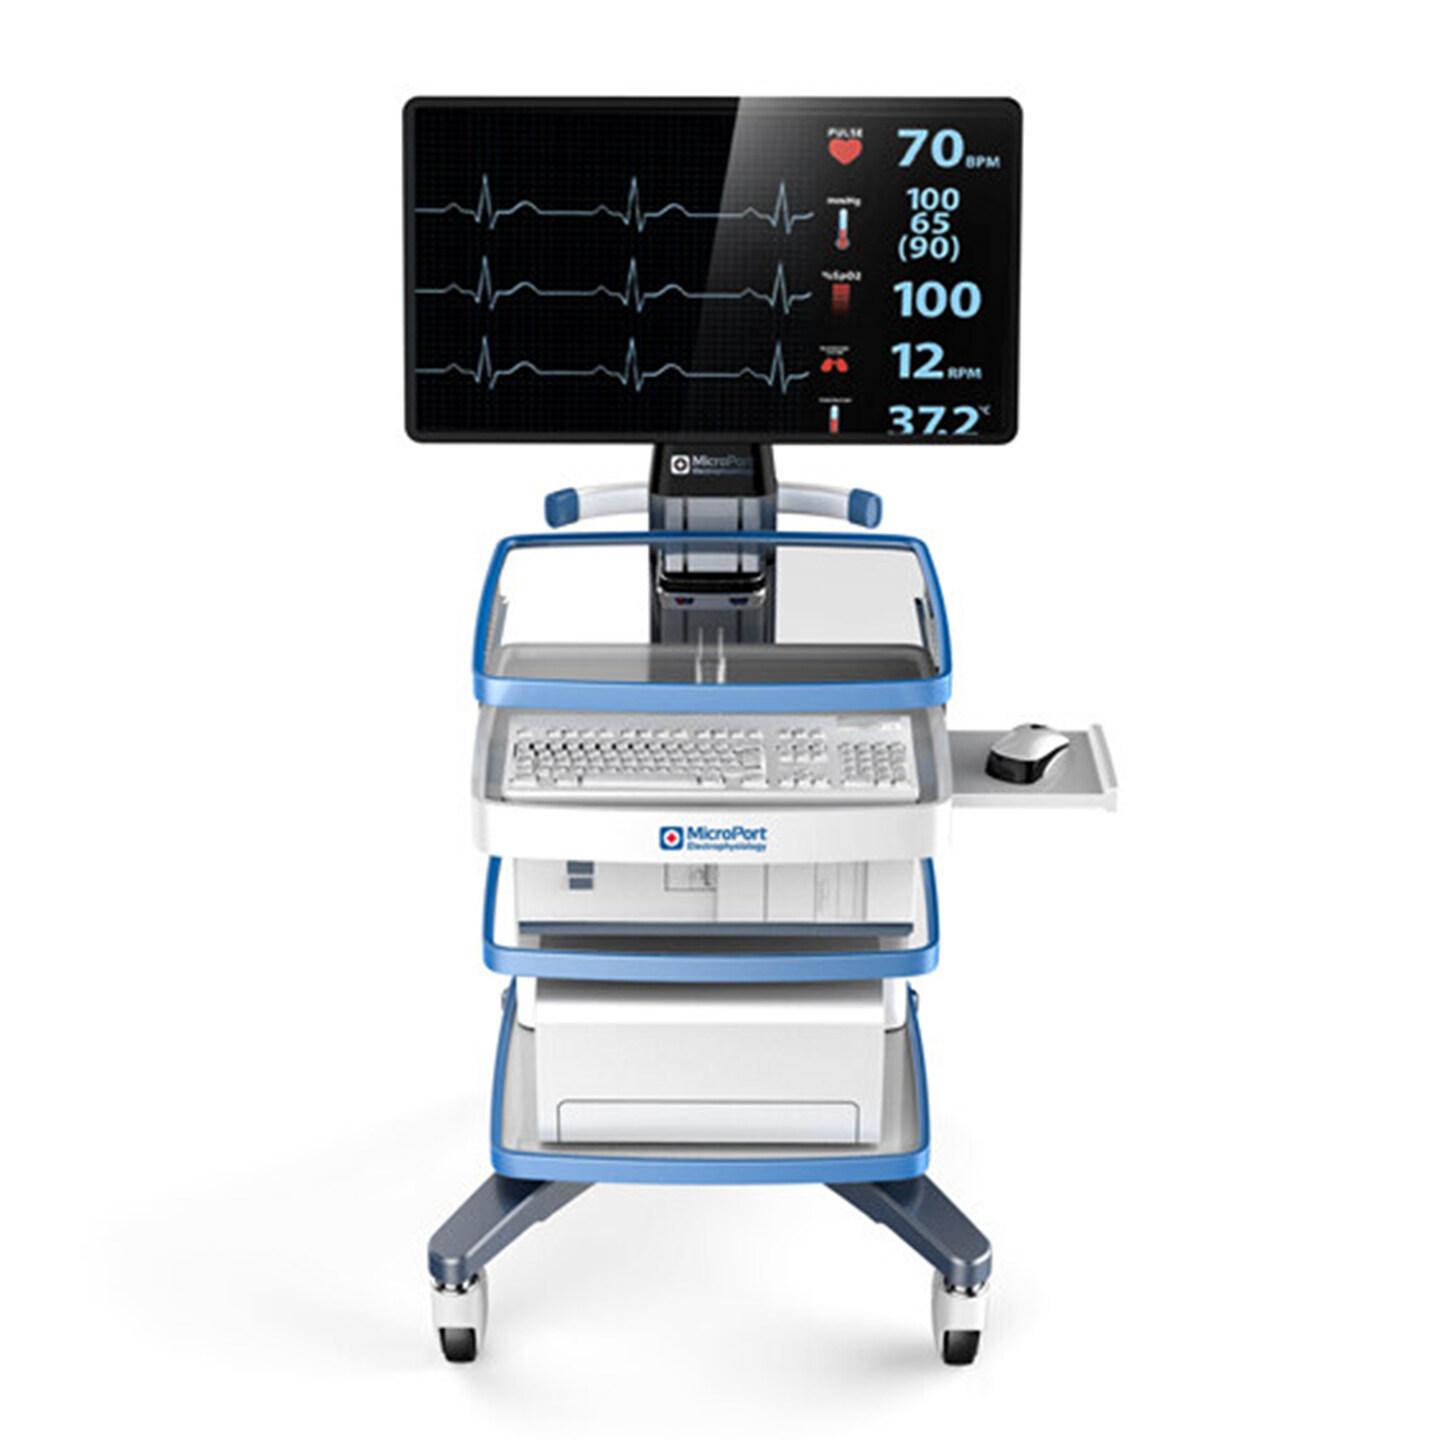

行业整体创新解决方案

摩登7咨询与设计以市场与技术的迭代更新为导向,业务深入智能制造、消费零售、交通出行、医疗健康、文化创意、公共服务等,多领域横向延伸,全行业覆盖。

摩登7是一家用咨询设计的能力,为垂直行业客户,提供产品创新价值的公司。摩登7坚持以用户体验为核心,致力于为企业提供行业整体创新解决方案。如需创新设计咨询,请联系专家团队。